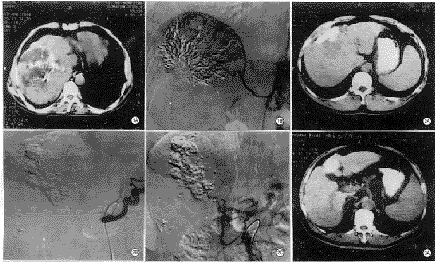

碘油组34例CT平扫显示的碘油沉积缺损区(除外肿瘤液化坏死本身不被碘油充填部分,该区可由CT值确定)与经动脉DSA所示肿瘤血管(包括残存瘤血管及侧支血供)及肿瘤染色区一致(图1)。其中12例行双期增强扫描,11例显示碘油缺损区不同程度强化,血管造影显示残存瘤血管及数量不等的侧支血供,侧支血管分别来自右膈下动脉、肠系膜上动脉、胃十二指肠动脉等;另1例CT平扫示碘油沉积缺损,呈片状低密度病灶,双期增强扫描示缺损低密度区未见明显强化。腹腔动脉造影示脾动脉、胃左动脉显影,肝总动脉及其各级分支未显影,行肠系膜上动脉的胰十二指肠下动脉微导管造影见肝总动脉及其各级分支显影,脾动脉及腹腔动脉淡薄显影,碘油缺损低密度区见少许肿瘤血管,染色淡薄(图2)。另3例CT平扫碘油沉积良好,无明显缺损,余肝实质未见异常密度影,但血管造影发现新病灶,后经导管CTA扫描证实(图3)。

微球组7例,CT平扫示瘤体不同程度缩小,中心见片状液化及气化坏死密度改变,双期增强示瘤体边缘部呈不规则厚壁状强化,4例门脉期强化程度明显高于动脉期,中心坏死区无强化。血管造影显示边缘部肿瘤血管及环状染色(图4)。

图1 A.CT平扫示肝右叶肝癌栓塞术后近膈顶部碘油沉积缺损。B.血管造影示该缺损区由粗大的右膈下动脉供血 图2 A.CT扫描示肝右叶前段缺损低密度区,增强时无明显强化。B.腹腔动脉造影时肝总动脉及其分支不显影,脾动脉及胃左动脉显影。C.肠系膜上动脉胰十二指肠下动脉造影时,胃十二指肠动脉、肝固有动脉及其分支、肝总动脉、脾动脉显影,提示肝动脉活瓣阻塞 图3 A.CT平扫见肝左叶碘油沉积良好,余实质未见明显低密度病灶。B.经导管CTA显示肝右叶出现3个新病灶 图4 A.肝癌白芨微球栓塞后CT平扫示中央区液化及气化坏死。B.2周后双期增强扫描静脉期边缘部明显强化,中央坏死区无强化。C.肝动脉血管造影示瘤体边缘部花环状肿瘤血管及染色,中央部未见供血动脉